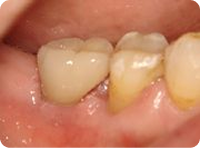

治療後

インプラントの土台に、セラミック冠をかぶせました。

見た目も天然の歯とほぼ変わらず、自然な仕上がりになりました。